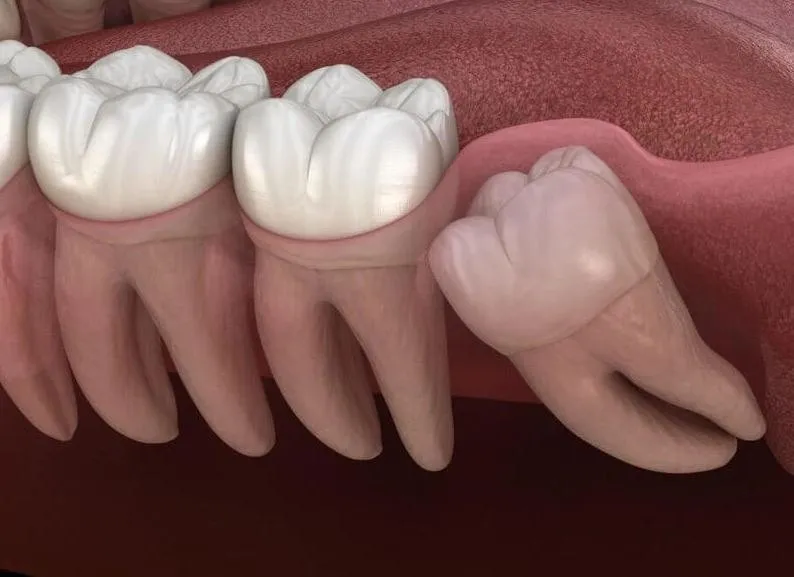

Răng 8 mọc ngầm là một hiện tượng nha khoa thường gặp, gây khó chịu và nhiều lo âu cho người bệnh. Khi nhắc đến răng 8